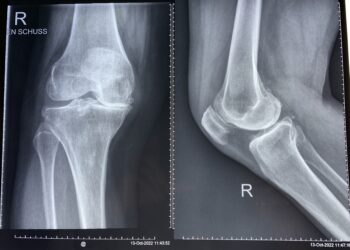

HÌNH ẢNH SAU THAY KHỚP GỐI